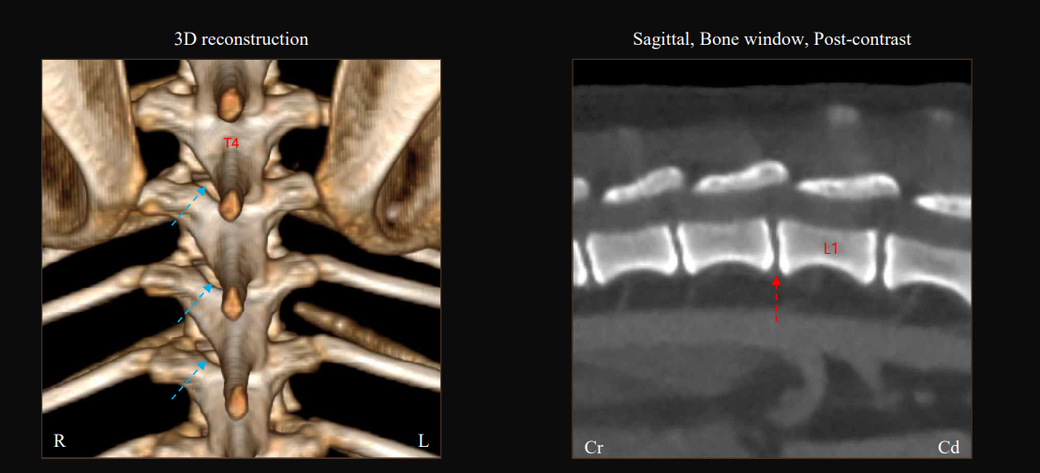

T4-6 vertebrae의 Rt. caudal articular process의 defect 확인됩니다. (→)

• T13-L1 vertebrae의 IVDS(intervertebral disc space)가 주변에 비해 좁게 확인됩니다.

T13-L1 vertebrae의 IVDS가 주변에 비해 좁게 확인되어 IVDD 가능성

고려됩니다.